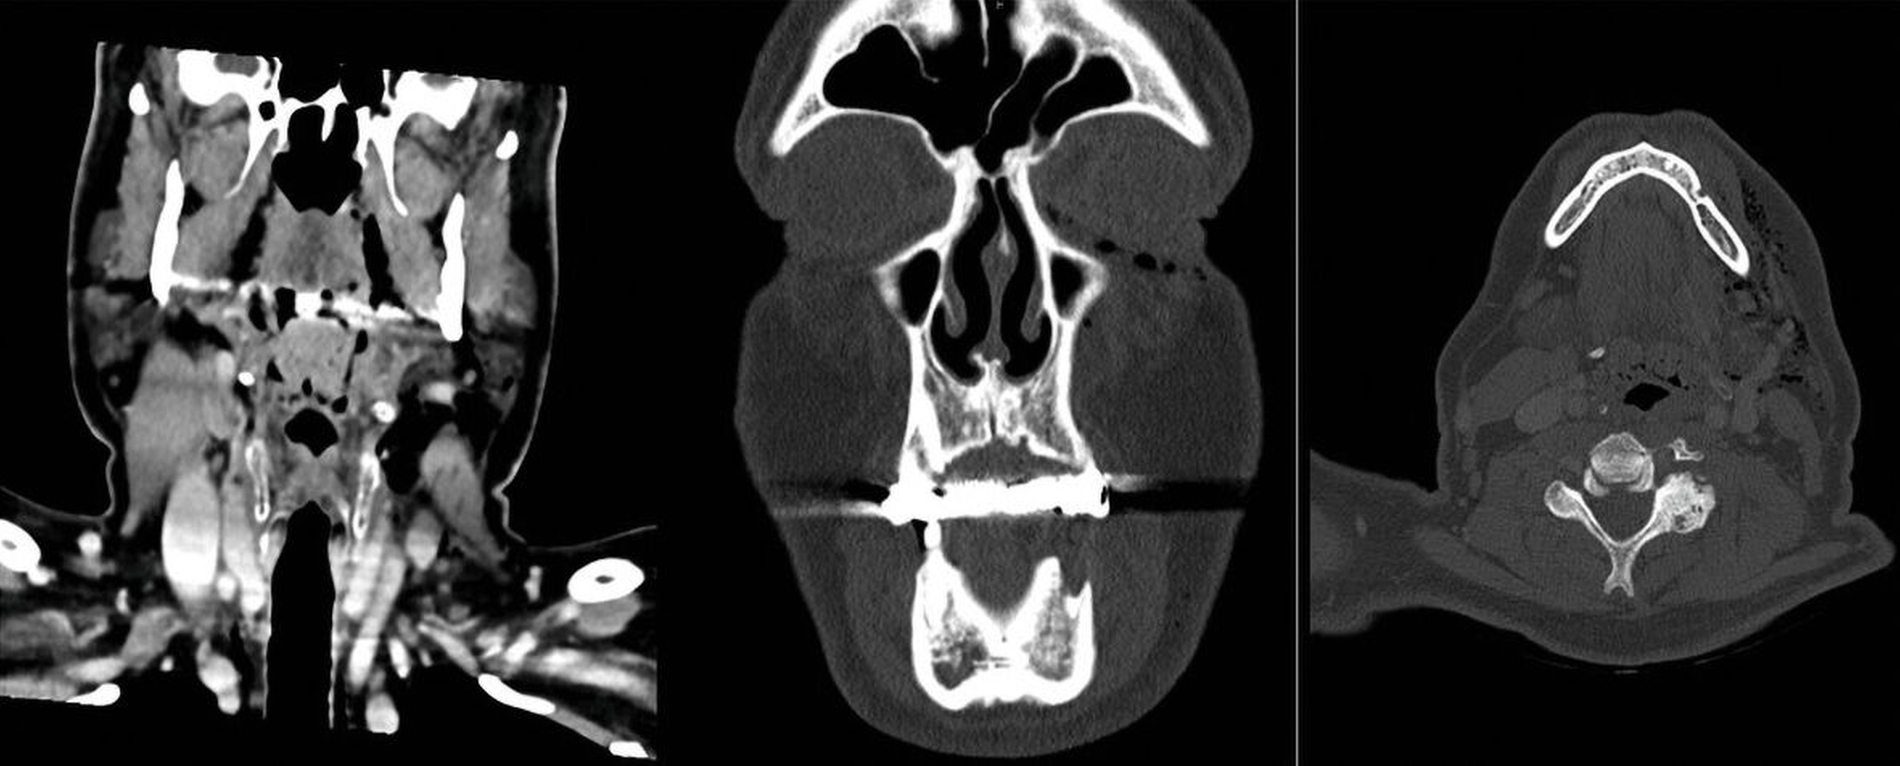

Die klinische Untersuchung ergab eine linksseitige Gesichtsschwellung mit tastbarem subkutanem Krepitus. In der anschließenden Kontrastmittel-gestützten Computertomografie von Kopf, Hals und Thorax zeigte sich ein ausgeprägtes zervikales Weichteilemphysem mit mediastinaler Ausdehnung sowie eine Radix relicta Regio 35 (Abbildungen 1 und 2). Hinweise auf eine Fraktur, einen Abszess oder eine intrathorakale Ursache bestanden nicht. Die radiologischen Befunde legten eine dentogene Ursache nahe, wobei insbesondere die Anwendung von Druckluftinstrumenten im Rahmen der vorangegangenen zahnärztlichen Intervention als auslösender Faktor infrage kam.